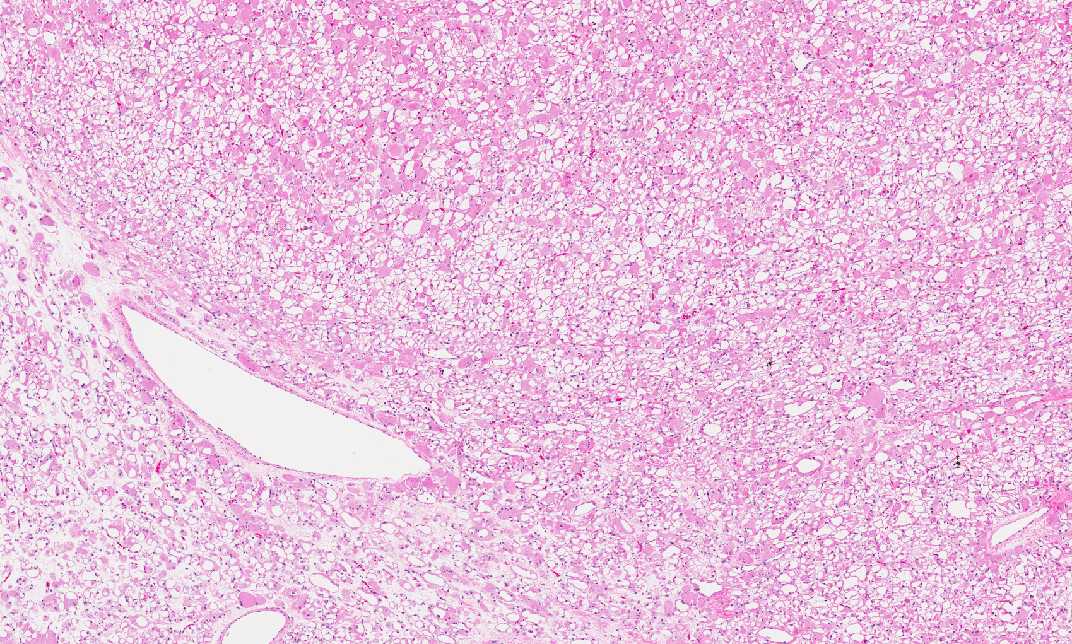

Histologically, the tumor is a well

circumscribed neoplasm with pushing margin. The tumor cells are

large and polygonal with one or two small, bland, and eccentrically

placed nuclei. While a significiant number of the tumor cells have a

fine granular, amphophilic to eosinophilic cytoplasm , many tumor

cells are dominated by a large centrally located vacule that pus the

cytoplasm to the periphery to become a rim (Area 1). In some cells,

bright eosinophilic rods can be seen (Area 2) and these material

represents Z-band material. Prominent nucleoli are noted in some of

the tumor cells. Mitoses are not readily seen and there is no

hemorrhage or necrosis.

Some of the vacuolated cells has a

central mass of stellate cytoplsm with thin strands connected to a

condensed rim of cytoplasm at the periphery (spider cells).

The tumor cells are separated by thin

fibrous septa and narrow vascular challesls.